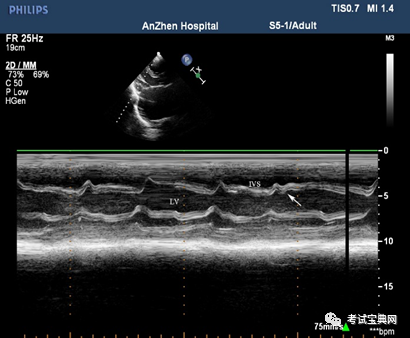

3.超声心动图:临床最常用的无创检测手段

典型表现为心包增厚、黏连心脏变形 , 室壁活动减弱 , 室间隔舒张期矛盾运动 , 即室间隔

抖动征) , 下腔静脉增宽且不随呼吸变化

文章插图

缩窄性心包炎室间隔异常运动